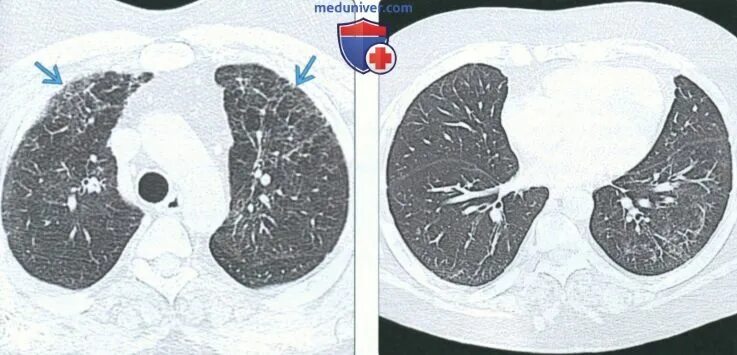

Гипостатические изменения кт